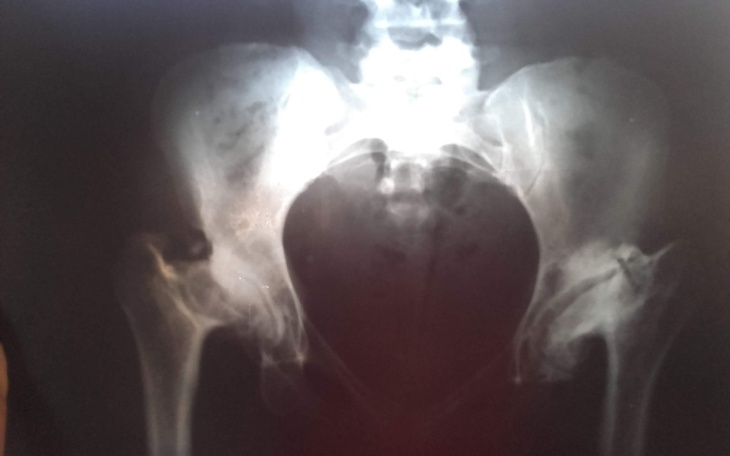

Jestem osobą niskiego wzrostu i z tego powodu żaden szpital w Polsce nie chce się podiąć rekonstrukcji moich stawów biodrowych aby przywrucić mi sprawność.

Zdjęcie przedstawiające stawy jest tragiczne jak się udaje do lekarza to on chodzi po kolegach i je pokazuje i wszyscy rozkładają ręce. A mój stan się cały czas pogarsza.

Mogę udostępnić dokumentację medyczną.